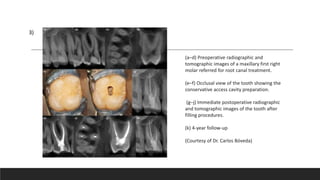

(a–d) Preoperative radiographic and

tomographic images of a maxillary first right

molar referred for root canal treatment.

(e–f) Occlusal view of the tooth showing the

conservative access cavity preparation.

(g–j) Immediate postoperative radiographic

and tomographic images of the tooth after

filling procedures.

(k) 4-year follow-up

(Courtesy of Dr. Carlos Bóveda)